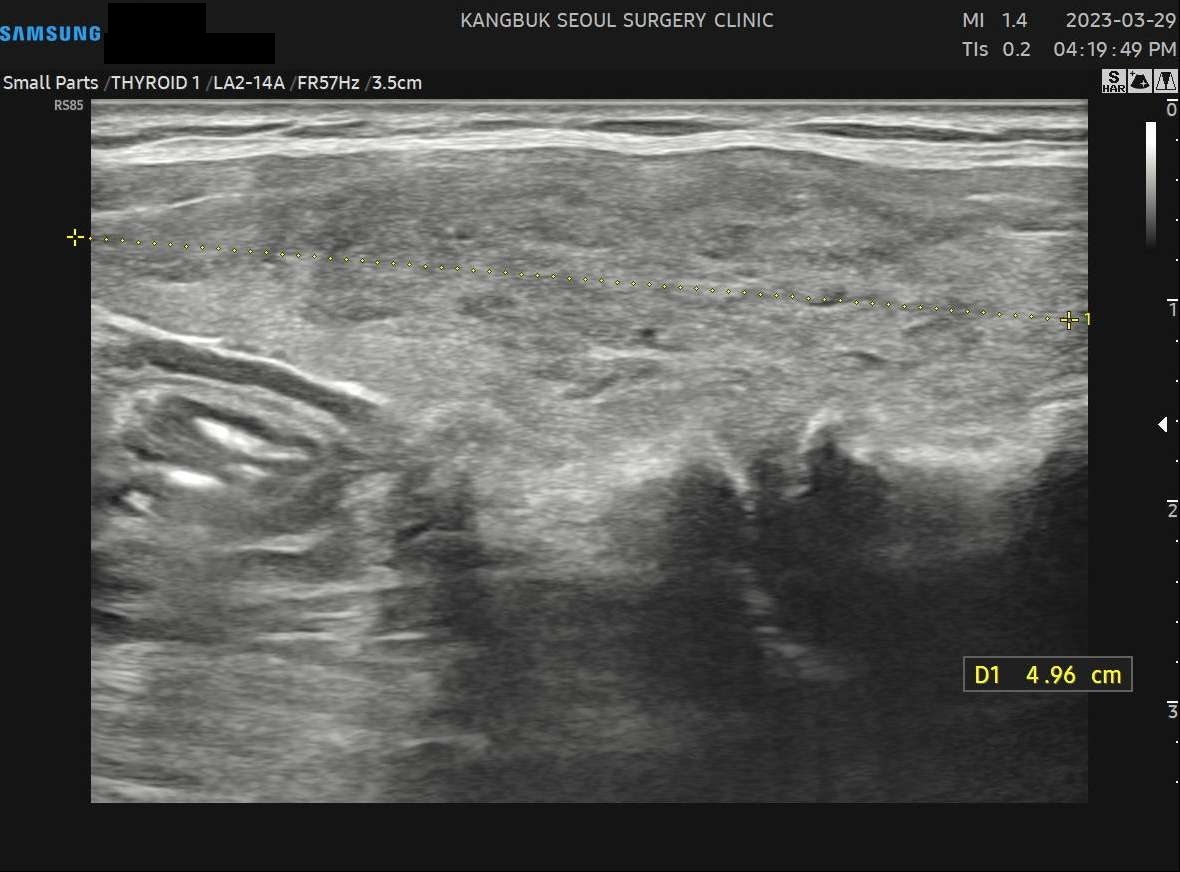

사례 1

수술 전(4.96cm)